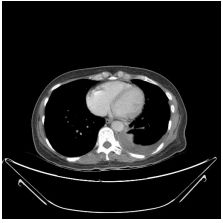

3. This 72-year-old diabetic man was taken to ER for productive cough for 10 days, and rapid progressive dyspnea for 2 days. He also had fever and chill for a week.